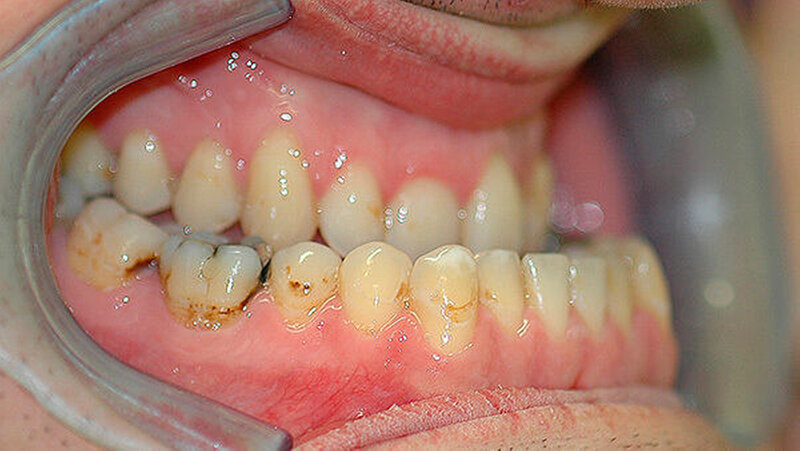

Der Patient stellte sich erstmals 2010 in der Stuttgarter MKG-Spezialsprechstunde vor. Im ersten Schritt wurde der Tumor an der Hirnanhangdrüse über die Nase entfernt. In interdisziplinärer Zusammenarbeit mit einem Fachzahnarzt für Kieferorthopädie wurden im ersten Behandlungsabschnitt die Zahnbögen ausgeformt. Um den Oberkiefer in der Breite zu dehnen, führten die Stuttgarter Zahnärzte im Oktober 2012 eine chirurgisch unterstützte Gaumennahterweiterung durch.

Das deutlich harmonischeres Profil drei Monate nach der Operation: Im Mai des nachfolgenden Jahres wurden die Metallplatten in einem ambulanten Eingriff wieder entfernt. Eine Multibandapparatur hält die Zähne noch "in der Reihe". Der Patient kann heute dank der individuellen innovativen Behandlung ein normales Leben führen, die Gesichtsästhetik und seine Kaufunktion sind vollständig wiederhergestellt.